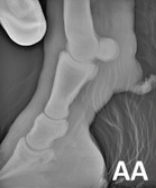

RX Images

In the 2013 Verena K. Affolter (U.C.Davis) study into CPL in Draft Horses there is a brief list of other potential diagnostics including lymphoscintigraphy and lymphangiogram. These procedures are expensive, invasive and unnecessary. Radiographs will show the extent of the folds but again are a surplus cost and show nothing that we can’t already see and feel, with regards to the CPL.